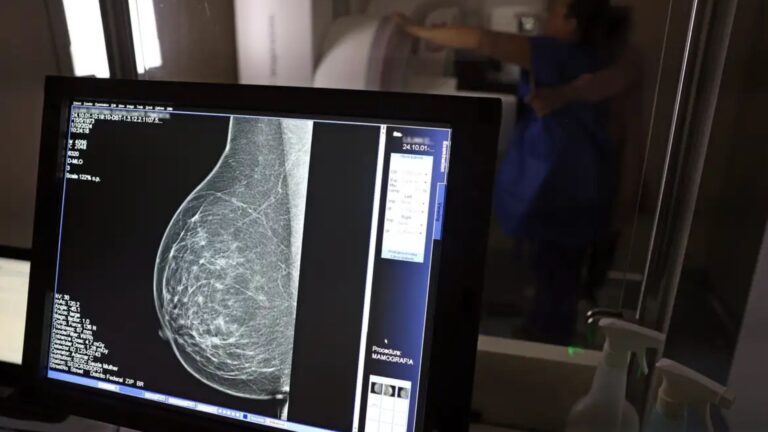

O direito já estava incluído na CLT desde 2018. A partir de agora, as empresas passam a ser obrigadas a divulgar essa informação, além de outras relacionadas a campanhas oficiais de vacinação contra o HPV e sobre o acesso a serviços de diagnósticos de cânceres de mama, próstata e de colo do útero.

O texto estende o uso das folgas também para a realização de exames preventivos do HPV, além dos de câncer que já estavam previstos na legislação anterior. A a Lei 15.377 foi sancionada pelo presidente Luiz Inácio Lula da Silva, e publicada na edição do Diário Oficial da União (DOU).